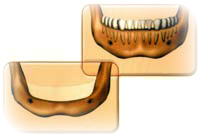

Атрофия кости в боковых отделах челюстей

При утрате боковых зубов происходит проваливание кожи лица в боковых отделах в результате атрофии кости челюстей. Зубы в переднем отделе челюсти начинают смещаться вперед и в стороны (как веер) из-за изменения прикуса, кроме того, опускаются уголки рта. В результате потери высоты лица изменяется облик человека. Если утраченные боковые зубы будут замещены частичным съемным протезом (например, бюгелем), процесс рассасывания кости ускоряется в результате давления со стороны протеза на десны и подлежащую кость во время жевания. Замена утраченных зубов с помощью мостовидных протезов с опорой на имплантаты позволяет сохранить гребень и предотвратить утрату прикуса и проваливание лица, что происходит при утрате зубов.

При утрате всех зубов рассасывание кости начинает происходить очень быстро. Кроме того, по мере атрофии кости происходит смещение мест прикрепления мышц. Из-за потери поддержки западают губы и образуются морщины. Полная утрата зубов и значительная резорбция костной ткани челюстей приводит к возникновению проблем со здоровьем, поскольку человек не в состоянии полноценно питаться и переваривать пищу.

Если утраченные зубы будут замещены полным съемным протезом, то это приведет к потере поддержки губ и щек. Съемные протезы ускоряют процесс рассасывания кости в результате давления на десны и подлежащую кость во время жевания. По мере атрофии тканей приходится проводить перебазировку съемного протеза (т.е. делать его толще), чтобы компенсировать потерю кости. Замена утраченных зубов с помощью съемных или мостовидных протезов с опорой на имплантаты позволяет сохранить гребень и предотвратить проваливание лица, что происходит при утрате зубов